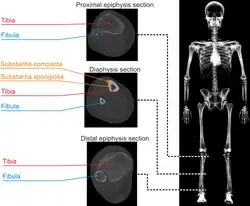

Lékařské záznamy rentgenového záření (CT) lze použít v biomechanice při tvorbě anatomických počítačových modelů lidských tkání vč. vyšetřování jejich struktury, hustoty a modulu pružnosti. Takto získané výsledky je možno použít také pro 3D tisk modelů orgánů či navržených implantátů. Podobné využití je také v paleontologii a archeologii při zkoumání struktury fosilií, mumií atp. Dalším cíleným zaměřením je také navigace lékařů při chirurgických úkonech (komplikované zlomeniny, vnitřní fixace, zevní fixace aj.).

- Příklad aplikace RTG záření v biomechanice[2]

Nehomogenní materiál, lidská tibie (zpracování CT snímků, separace kostní tkáně od měkkých tkání, tvorba CAD/MKP modelu v sw MIMICS a získané rozložení modulu pružnosti)

Nehomogenní materiál, lidská tibie (zpracování CT snímků, separace kostní tkáně od měkkých tkání, tvorba CAD/MKP modelu v sw MIMICS a získané rozložení modulu pružnosti) -

Nehomogenní materiál, lidská tibie (zpracování CT snímků, separace kostní tkáně od měkkých tkání, tvorba CAD/MKP modelu v sw MIMICS a získané rozložení modulu pružnosti)

Nehomogenní materiál, lidská tibie (zpracování CT snímků, separace kostní tkáně od měkkých tkání, tvorba CAD/MKP modelu v sw MIMICS a získané rozložení modulu pružnosti)